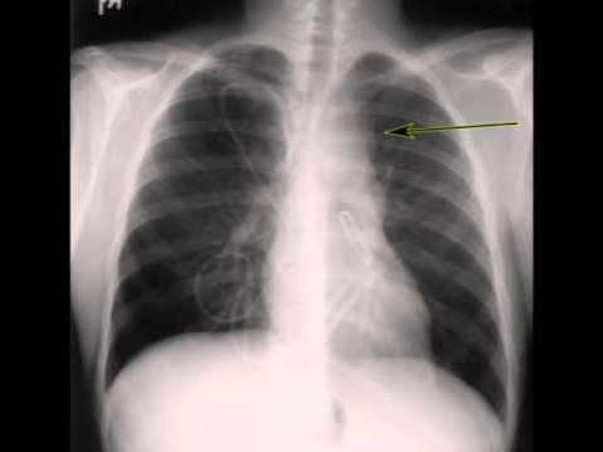

with all the new Hopes and Desires. But on the same day, Prem diagnosed with Hodgkin Lymphoma Stage(1V) Cancer but then he is fighting for his life by accumulating all his confidence, courage, strength and positivity. He is being treated till date and has undergone a chemotherapy for 3 tumors’ (Neck, Lung and Liver) from past 8 months. Current medication has no luck and indeed the tumor sizes have been increasing drastically in Lungs and Liver. Hence, doctors have suggested to go with higher treatment that includes Brentuximab-12 vials and Bone Marrow transplantation. A-Vial of Brentuximab itself costs around 1.5 lakhs. This treatment is not being covered by Health Insurance Scheme. Therefore, it would be helpful if you can contribute some amounts which helps in Prem's treatment and save him from cancer and can lead a normal life again.

Request you all to come forward and please help him. Any contribution will immensely help him a lot. I urgently need your support. I urge you to share this campaign link with your friends and family as much as possible. Enclosed all the Biopsy reports, PET CT reports and the X-Ray reports.